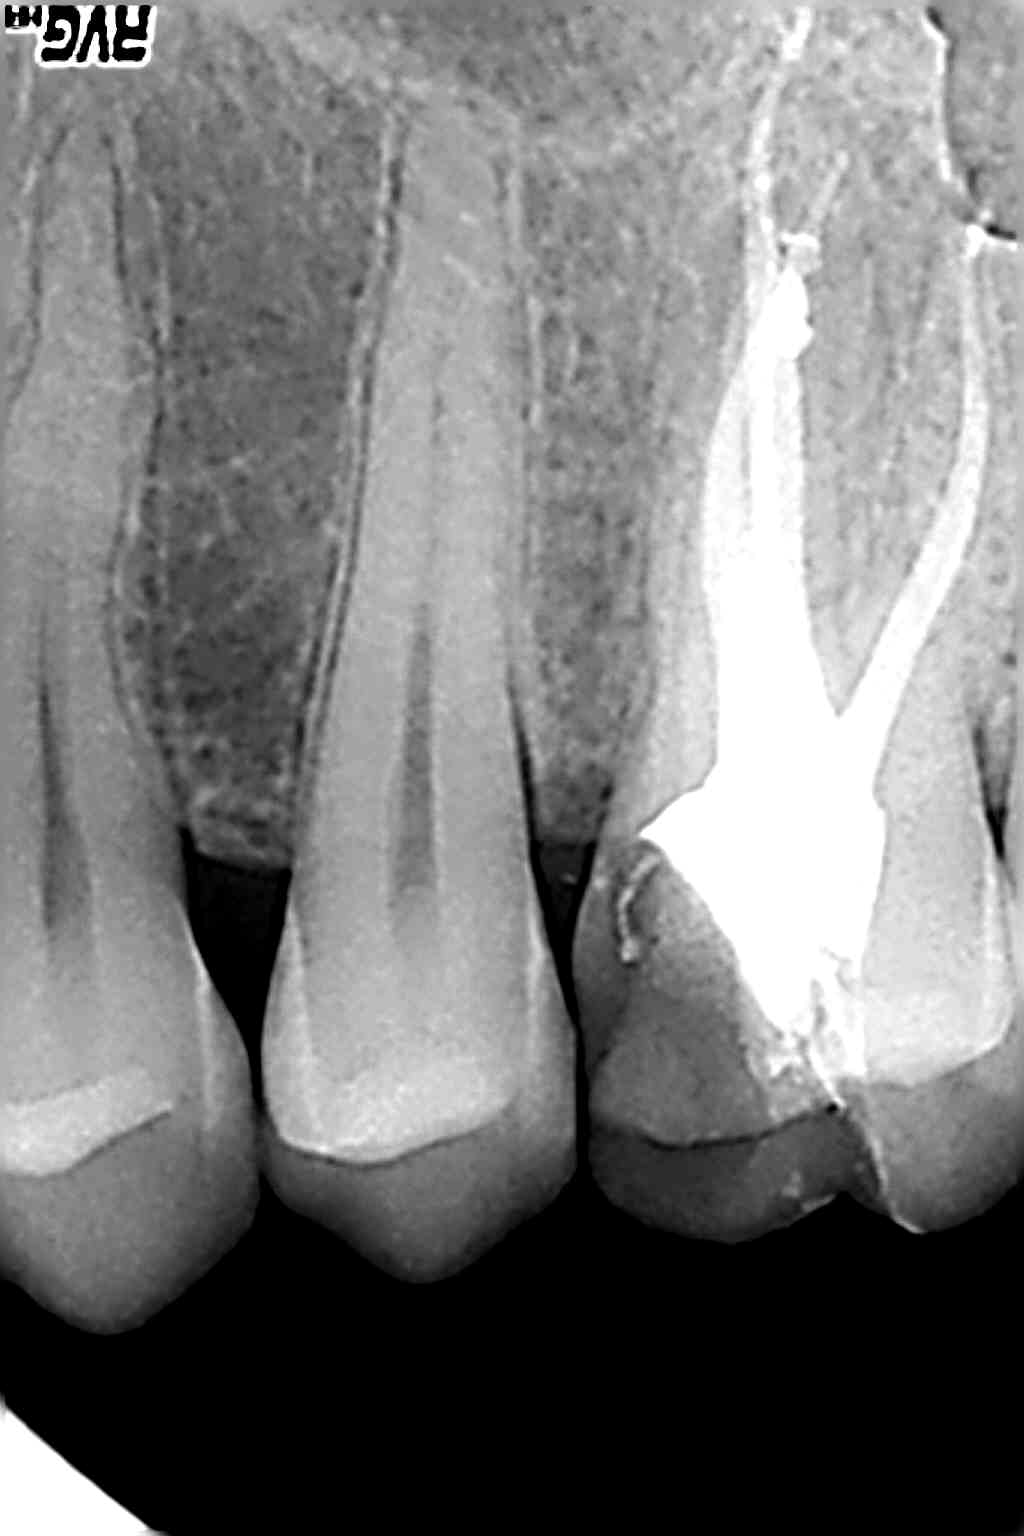

Par ex endo 26

Deux radios : la première avec l'ancien capteur trophy

et la seconde avec le nouveau 6100.

Sérieusement vous voyez quelque chose sur le deuxième cliché ?

Le premier pris il y a 2 mois, lors de l'endo avec le trophy, et le deuxième cliché avec le kodak, je n'arrive pas à dire si c'est en voie de guérison :((

Même avec le filtre de netteté, en bidouillant les contrastes, j'y vois quedal :(